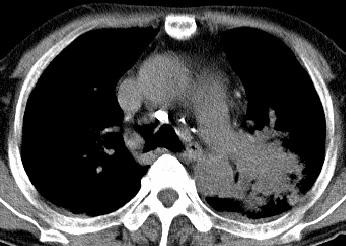

以下是引用xianxianzhongyi在2008-4-20 14:44:00的发言:[br]本人愚见:次病例短短两月的时间,呈现如此大面积实变,病变增长过于迅速,此其一。其二,病变在动脉早期既有明显强化。其三,左上叶后段及下叶背段多叶受累。其四,肺门及纵隔内未见明显肿大的淋巴结。估计层面较厚段支气管显示不清。 诊断:炎性实变可能性大。

以下是引用光影相伴在2008-4-20 14:39:00的发言:[br]支持:1)左侧中央型肺癌伴左肺上叶阻塞性肺炎。、[br] 2)双侧少量胸腔积液。